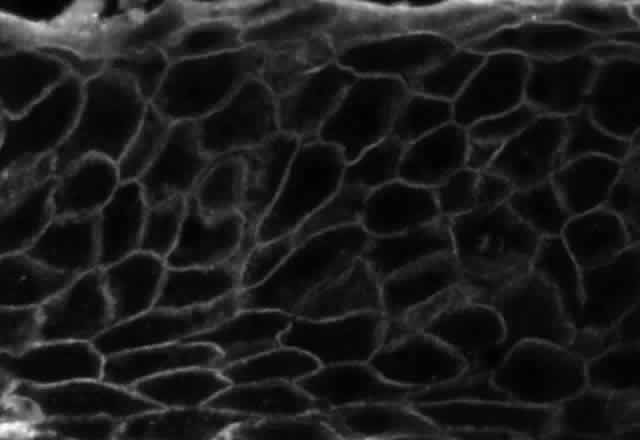

Pemphigus can be differentiated from bullous pemphigoid and from cicatricial pemphigoid on histologic and immunologic bases. Whereas the bullae in pemphigus are intraepidermal, those occurring in bullous pemphigoid and in cicatricial pemphigoid are subepidermal, between epidermis and dermis, or between mucosa and submucosa. Acantholysis is not present in the latter two conditions.5 In bullous pemphigoid and in cicatricial pemphigoid there are tissue-fixed immunoglobulins in the subepidermal basement membrane zone (Fig. 2).11 This is in contrast to the interepidermal fixation of antibodies (Fig. 3) seen in pemphigus (Table 1).

The diagnosis of OCP is extremely important, given the natural history of the disease, the effectiveness but potential toxicity of therapy, and the potential confusion in differentiation from other causes of chronic cicatrizing conjunctivitis (Table 2). The clinical diagnosis requires immunohistochemical confirmation prior to institution of therapy20; the diagnosis is confirmed by the demonstration of one or more immunoreactants at the epithelial basement membrane zone (see Fig. 2).